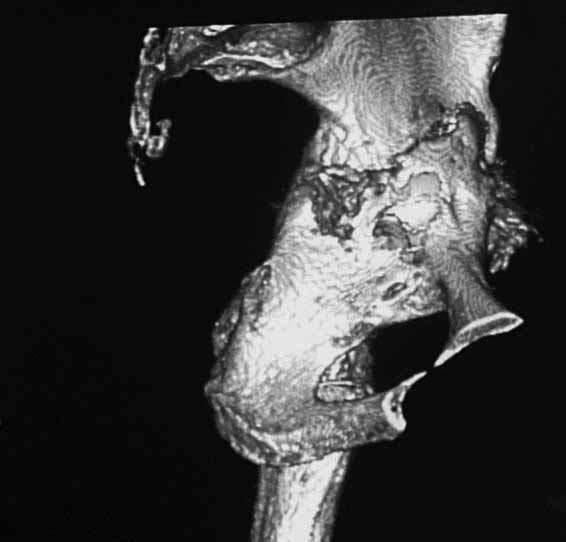

Уважаемые коллеги. Хотелось бы услышать мнения и советы по представляемому случаю. Пациентка 45 лет. Бесцементное эндопротезирование левого тазобедренного сустава 6 лет назад (впадина RM, Mathys, металл-металл, ножка Зульцеровская). За 10 лет до протезирования – коррегирующая остеотомия бедренной кости, которая не срослась в течение года до удаления пластины, а затем срослась в течение 3 месяцев иммобилизации в кокситной повязке. После протезирования получилось наблюдать пациентку почти постоянно, поскольку через 2 года синтезировал ей лодыжки на оперированной стороне, затем, через несколько месяцев удалил фиксаторы, а в 2009г. резецировал мениск на противоположной стороне. Боли все эти годы не беспокоили. Пациентка чуть выше среднего роста, вес тела нормальный. Физические нагрузки переносила хорошо. Работает на 7 этаже без лифта. Год назад экстирпация матки по поводу лейомиомы больших размеров. Несколько месяцев назад появились боли в области левого тазобедренного сустава. При рентгеновском и КТ исследованиях (июль с.г.) – нестабильность тазового компонента. От предложенной замены протеза пациентка на тот момент, слава богу, отказалась. Через какое то время боли в области левого тазобедренного сустава практически полностью прошли, а около 2 месяцев назад появилось ощущение патологической подвижности таза и боли в паху справа, которые через некоторое время уменьшились, а потом снова усилились после значительных физических нагрузок (много ходила по песку на пляже, носила тяжести). Ежедневно принимала диклофенак. На рентгенограммах – переломы правой лонной кости. Сейчас госпитализирована из-за болей в паху справа. Боли слева не беспокоят. На фоне снижения нагрузок в стационаре боли значимо уменьшились. Способна ходить без средств дополнительной опоры.В анализах крови чуть повышены трансаминазы и гамма-ГТ, моча без особенностей.

Вопросы: -правильно ли я расцениваю переломы как стрессовые на фоне неполноценного таза (pelvic insufficiency stress fractures)? -Можно ли так же расценить ситуацию на стороне протеза и, соответственно, не торопиться с ревизией, рассчитывая на вторичную стабилизацию? Уж больно не хочется менять ножку. -Если думать о ревизии, то когда? На представленных снимках тазобедренный сустав до и сразу после операции, затем 2 снимка 2009г., когда ничего не беспокоило, затем КТ 2-х месячной давности и вчерашние рентгенограммы обоих тазобедренных суставов.

При сравнении рентгенограмм можно увидеть насколько чашка переместилась от места своего первичного расположения. От опрокидывания ее удерживают конструкционные элементы "рожки". Без них ситуация, возможно, уже была бы катастрофической (чашка в тазу). Думаю надежды на вторичную интеграцию, могут быть обмануты и ревизии не избежать.